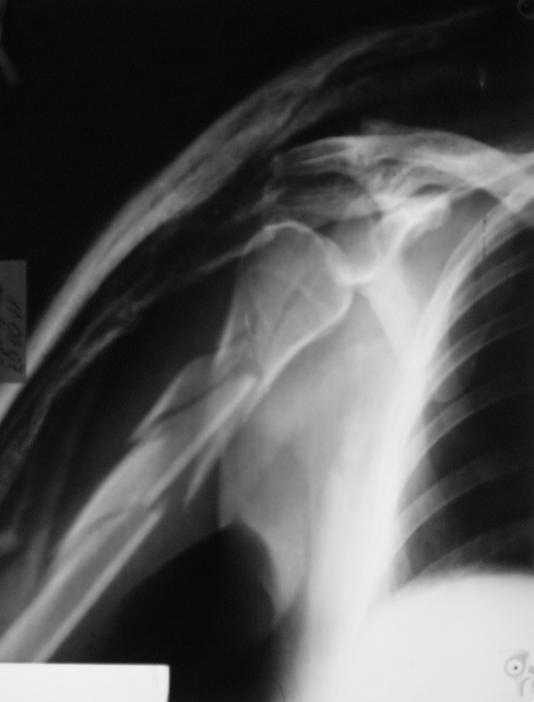

Re: Многооскольчатый перелом плечевой кости в В/3

Немножко переделал повязку с отведением, подправил, вот что получилось.

Перелом внутрисуставной, Вы уверены на счет Сармиенто? На первичном снимке не видно было перелома головки.